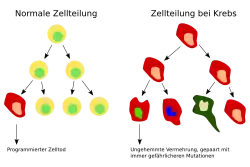

Krebs bezeichnet in der Medizin die unkontrollierte Vermehrung und das wuchernde Wachstum von Zellen, d. h. eine bösartige Gewebeneubildung (maligne Neoplasie) bzw. einen auch Krebsgeschwulst oder Malignom genannten malignen (bösartigen) Tumor. Bösartig bedeutet, dass neben der Zellwucherung auch Absiedelung (Metastasierung) und Invasion in gesundes Gewebe stattfindet. Im engeren Sinn sind die malignen epithelialen Tumoren (Karzinome), dann auch die malignen mesenchymalen Tumoren (Sarkome) gemeint. Im weiteren Sinne werden auch die bösartigen Hämoblastosen als Krebs bezeichnet, wie beispielsweise Leukämie als „Blutkrebs“.

Gutartige Tumoren wie Muttermale und Fettgeschwülste (Lipome) werden in der Fachsprache nicht als Krebs bezeichnet, aber sie können trotzdem gefährlich werden, da sie entarten können oder lebenswichtige Organe in deren Funktion beeinträchtigen (etwa der Kleinhirn-Brückenwinkeltumor). Krebs ist im allgemeinen Sprachgebrauch ein Sammelbegriff für eine Vielzahl verwandter Krankheiten, bei denen Körperzellen unkontrolliert wachsen, sich teilen und gesundes Gewebe verdrängen und zerstören können. Nach aktuellem Stand des Wissens entwickeln Plazenta-Säugetiere häufiger aggressive Epitheltumoren im Vergleich zu anderen Spezies, der Grund hierfür könnte die Evolution der feto-maternalen Immuntoleranz sein.[1] An sich kann unkontrolliertes Zellwachstum aber in allen mehrzelligen Lebewesen vorkommen. Krebs hat unterschiedliche Auslöser, die alle zu einer Störung des genetisch geregelten Gleichgewichts zwischen Zellzyklus (Wachstum und Teilung) und Zelltod (Apoptose) führen.

In einem gesunden Organismus werden die Zelltypen, aus denen sich die verschiedenen Gewebe der Organe aufbauen, in einem ausgewogenen artspezifischen Gleichgewicht gebildet und regeneriert, was als Homöostase bezeichnet wird. In diesem Zustand der Homöostase gibt es ein Gleichgewicht zwischen der Vermehrung von Zellen (Zellproliferation) und dem Zelltod. Der Hauptanteil des Absterbens von Zellen erfolgt dabei durch Apoptose, bei der die Zellen „Selbstmord“ begehen. In pathologischen Situationen kann dieses Absterben auch durch Nekrose geschehen. Bei Krebs ist dieses Gleichgewicht zugunsten des Zellwachstums verändert. Die Krebszellen wachsen dabei ungehindert, da hemmende Signale nicht erkannt oder nicht ausgeführt werden. Der Grund liegt in Defekten der Erbinformation, die durch Mutationen entstanden sind.

Etwa 5.000 der insgesamt 25.000 Gene des Menschen sind für die sichere Erhaltung der Erbinformation von einer Zellgeneration zur nächsten zuständig. Diese sogenannten Tumorsuppressorgene überwachen die korrekte Abfolge der Basenpaare in der DNA nach jeder Reduplikation, entscheiden über die Notwendigkeit von Reparaturvorgängen, halten den Zellzyklus an, bis die Reparaturen ausgeführt sind, und veranlassen gegebenenfalls einen programmierten Zelltod (Apoptose), falls die Reparatur nicht zum Erfolg führt. Daneben sind die Protoonkogene zuständig für die Einleitung oder den Unterhalt der Proliferation der Zelle und ihrer anschließenden Entwicklung zu einem bestimmten Zelltyp (Differenzierung).

Nach der heute als plausibel geltenden Theorie der Krebsentstehung (Karzinogenese) ist das primäre Krankheitsereignis eine Veränderung in einem dieser Wächtergene – entweder durch einen Kopierfehler oder seltener durch eine angeborene Mutation. Dieses Gen kann dann den von ihm überwachten Teilschritt nicht mehr korrekt begleiten, sodass es in der nächsten Zellgeneration zu weiteren Defekten kommen kann. Ist ein zweites Wächtergen betroffen, so potenziert sich der Effekt fortlaufend. Wenn auch Apoptose-Gene (z. B. p53) betroffen sind, die in einer solchen Situation den programmierten Zelltod auslösen müssten, werden diese Zellen potentiell unsterblich. Durch die Aktivierung der Protoonkogene wird ein Krebs zum Wachstum angeregt, was in einer Raumforderung und in Folge zu auftretenden Schmerzen führen kann. Zur Krebsentstehung sind mehrere solcher Mutationen notwendig (englisch multiple hit model).[20] Hierbei hat sich die Annahme von Peter Nowell bestätigt, dass zur Entstehung eines malignen Tumors mindestens sechs bis sieben Mutationen nötig sind.[21]

Die Proliferation einer in den relevanten Genen veränderten Zelle zu einem Zellhaufen vergrößert dabei entscheidend die Wahrscheinlichkeit für eine weitere relevante genetische Veränderung im Rahmen des Mehrschrittprozesses, da bei jedem Kopiervorgang der DNA Fehler entstehen können. Solche Veränderungen können auch durch äußere Einflüsse (z. B. krebserregende Stoffe, ionisierende Strahlung, Onkoviren) induziert werden, oder durch eine genetische Instabilität der veränderten Zellpopulation zustande kommen. Irritierende Reize können durch Erhöhung der Proliferation diesen Prozess beschleunigen. Während bei einigen Tumoren eine oder zwei Mutationen ausreichen können,[22] gibt es auch Tumoren, bei welchen bis zu zehn verschiedene Mutationen erfolgt sein müssen. Einige dieser notwendigen Mutationen können vererbt werden, was erklärt, dass auch sehr kleine Kinder an Krebs erkranken können und dass Krebs in sogenannten „Krebsfamilien“ gehäuft auftreten kann. Ein typisches Beispiel dafür ist das vererbbare Xeroderma pigmentosum. Bei nahen Verwandten von Patientinnen mit Brustkrebs ist die Wahrscheinlichkeit, Brustkrebs zu bekommen, doppelt so hoch wie in der übrigen Bevölkerung. In den dazwischenliegenden Schritten der Tumorentstehung (Promotion und Progression) spielen nicht genotoxische Prozesse eine große Rolle, was Beobachter dazu verleiten könnte, diese Einflüsse als eigentliche „Krebserreger“ einzustufen.